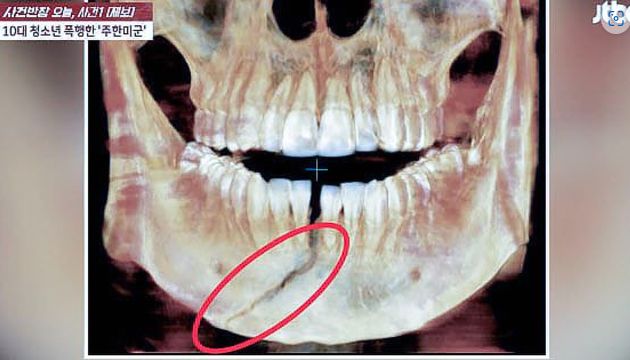

주한미군에게 폭행당해 턱뼈가 골절된 10대 남학생이 평생 후유장애가 남을 수 있는 중상을 입은것으로 알려졌다. /사진=JTBC사건반장 캡쳐

A군 아버지가 공개한 A군 X레이 사진을 보면 턱뼈가 골절됐다. A군 아버지는 "아들은 입안에 보철을 착용하고 고정한 상태로 8주간 있어야 한다"며 "워낙 정도가 심해서 평생 후유장애가 남을 수도 있다고 말하더라"라고 설명했다.